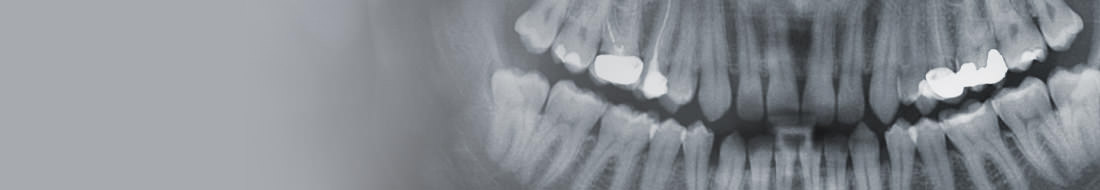

The extraction of wisdom teeth can be a simple, but also a difficult surgical procedure, and should only be performed by dental professionals with proper training and experience performing such extractions. The precise reasons why an individual’s wisdom teeth need to be extracted should be explained to them by their dentist, after an examination which almost certainly will need to include x-rays.